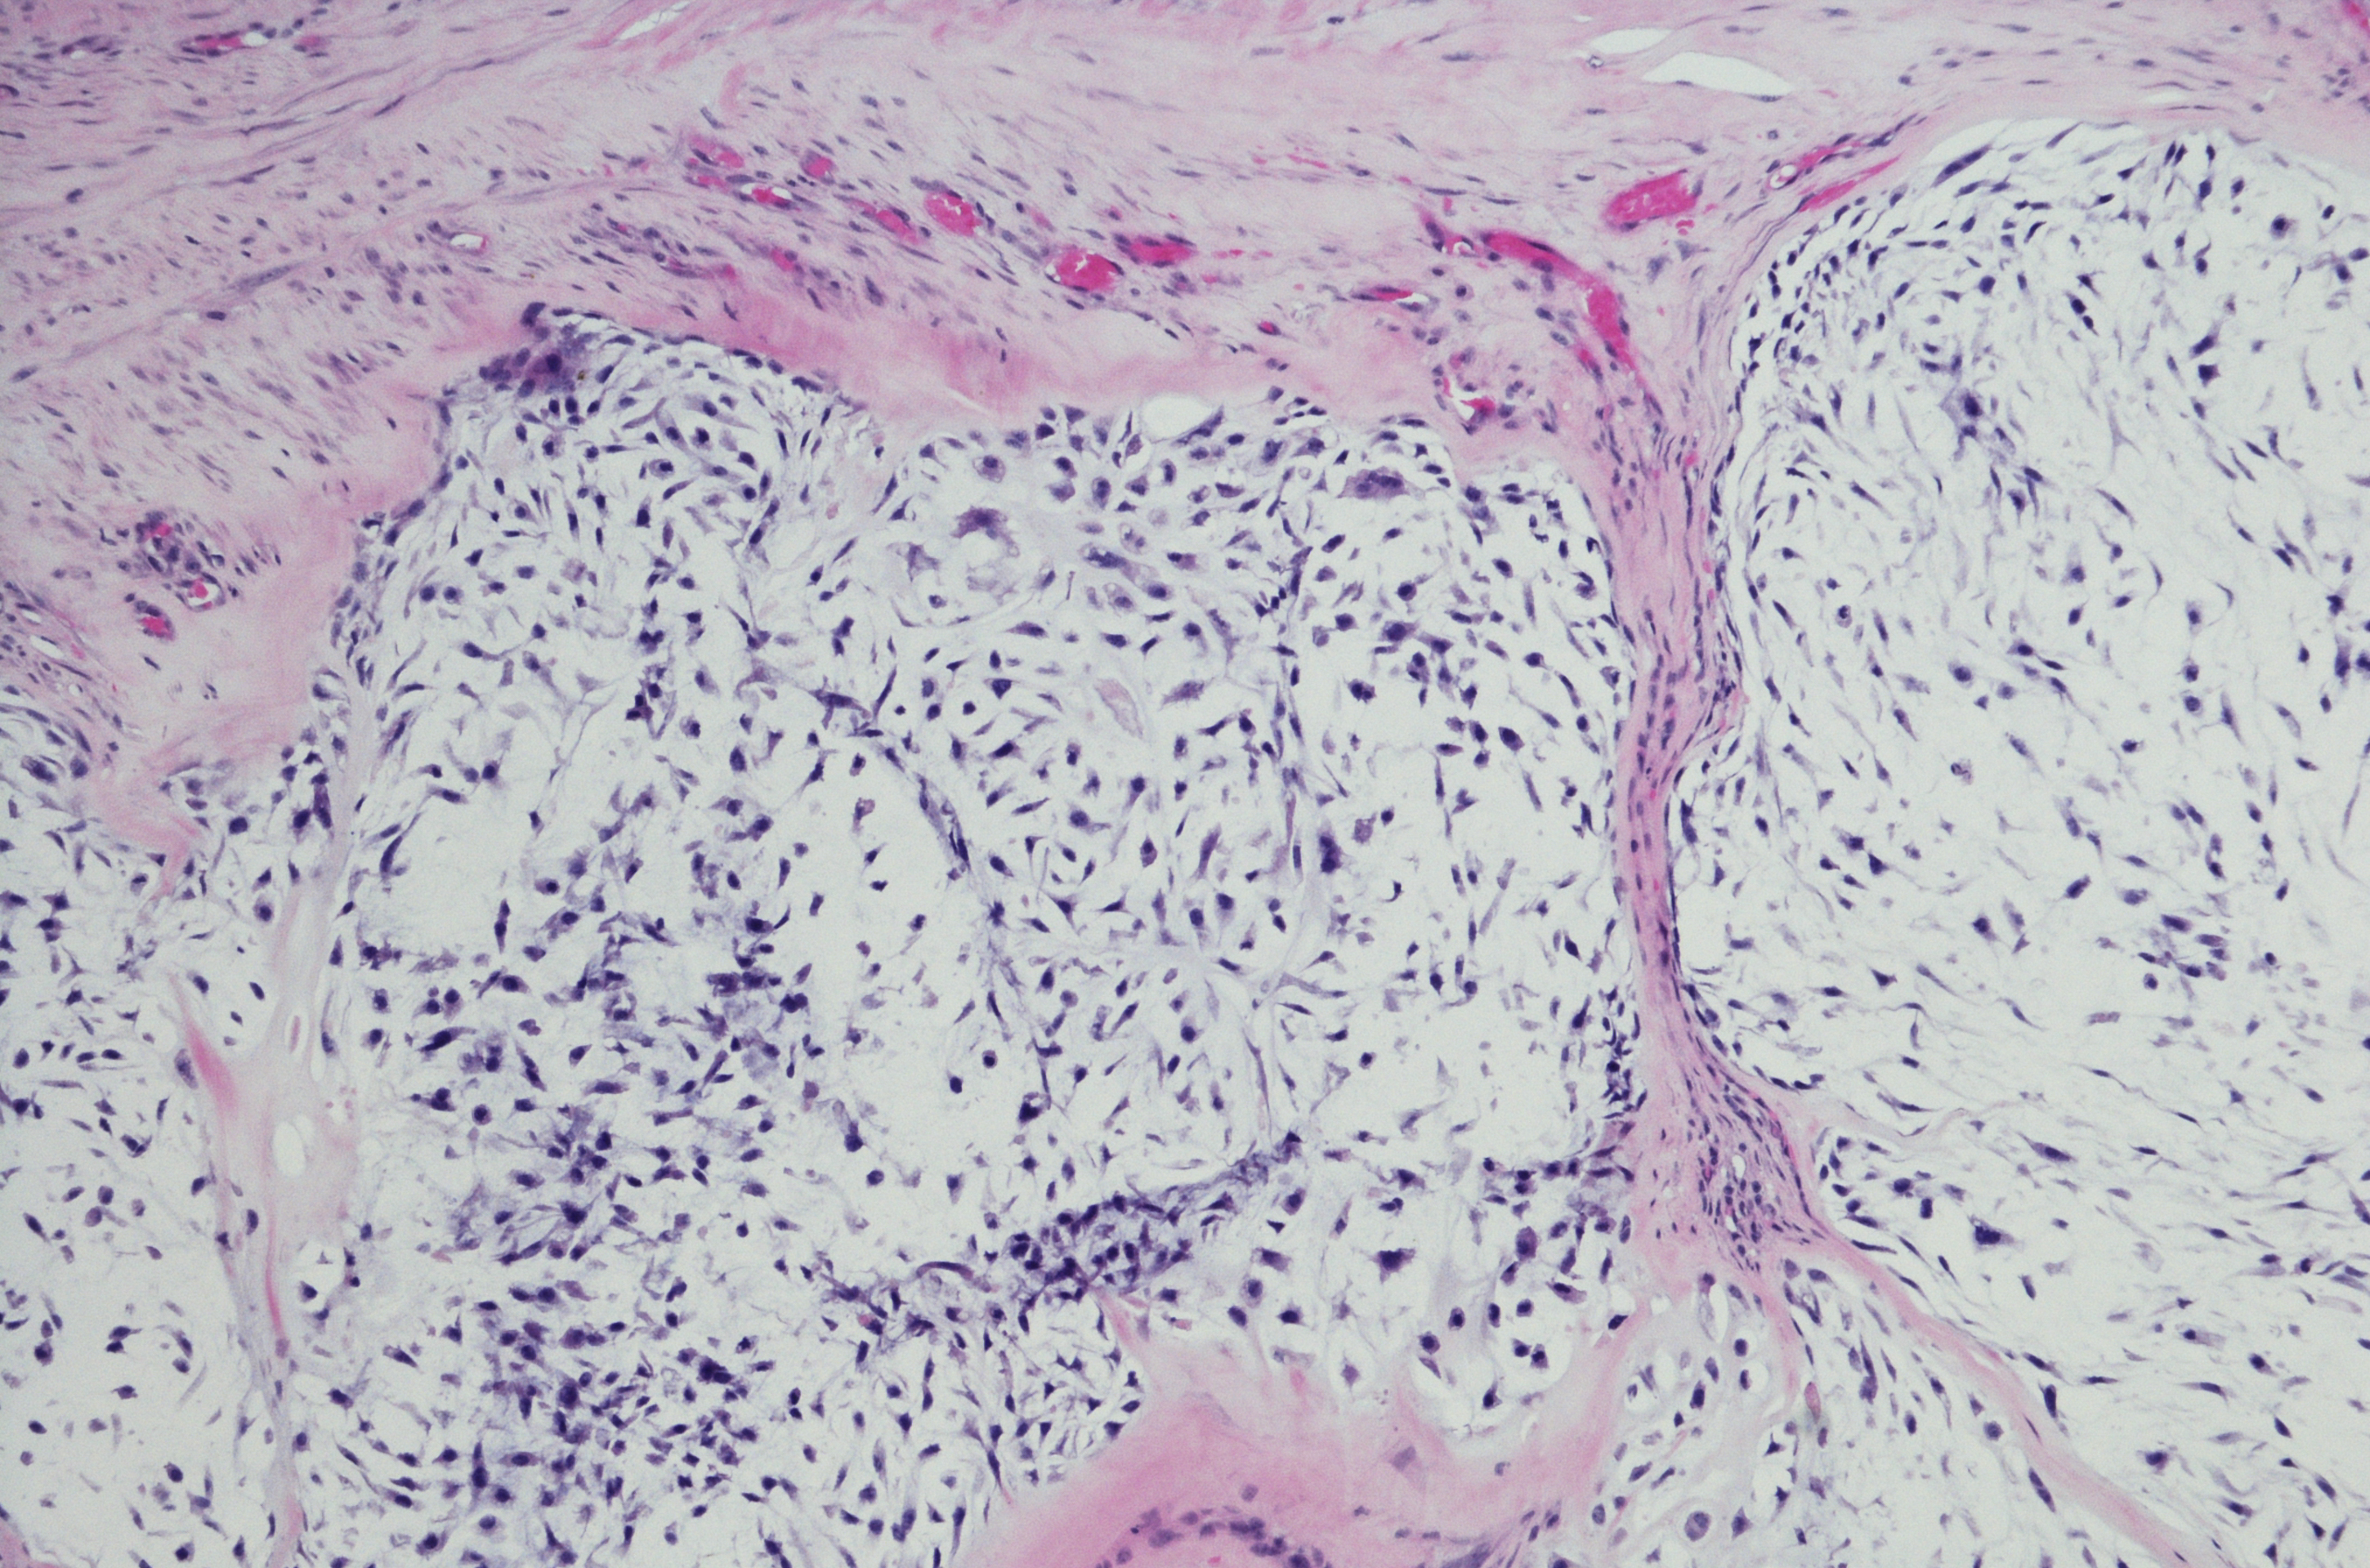

There are several subtypes of chondrosarcoma, named because of the way they appear under a microscope:

‘Conventional chondrosarcoma’ and ‘clear cell chondrosarcoma’ are most often low to medium grade tumours. They are generally not very aggressive and tend not to spread to other parts of the body.

‘Mesenchymal chondrosarcoma’ and ‘de-differentiated chondrosarcoma’ are higher grade, aggressive tumors that tend to spread throughout the body.

Chondrosarcoma is most often discovered through x-ray. Additional tests, including a bone scan, CT scan, MRI and/or PET scan will provide more detailed information, as it can be difficult to differentiate a benign bone tumour from chondrosarcoma. The surest way to diagnose, is through a biopsy procedure which will extract a sample of the cancer cells for analysis under a microscope.